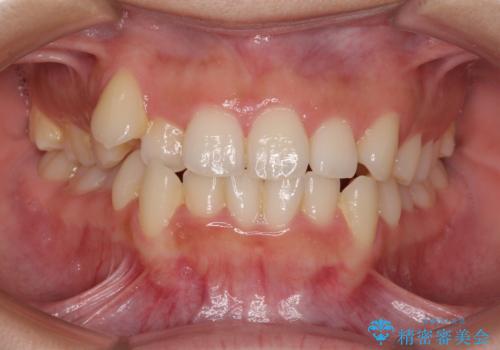

- 上下前歯のデコボコを気にして来院された患者様です。

上顎歯列が下顎の歯列に対して狭小であり、一部下顎の奥歯が上顎よりも外側に位置している状態でした。